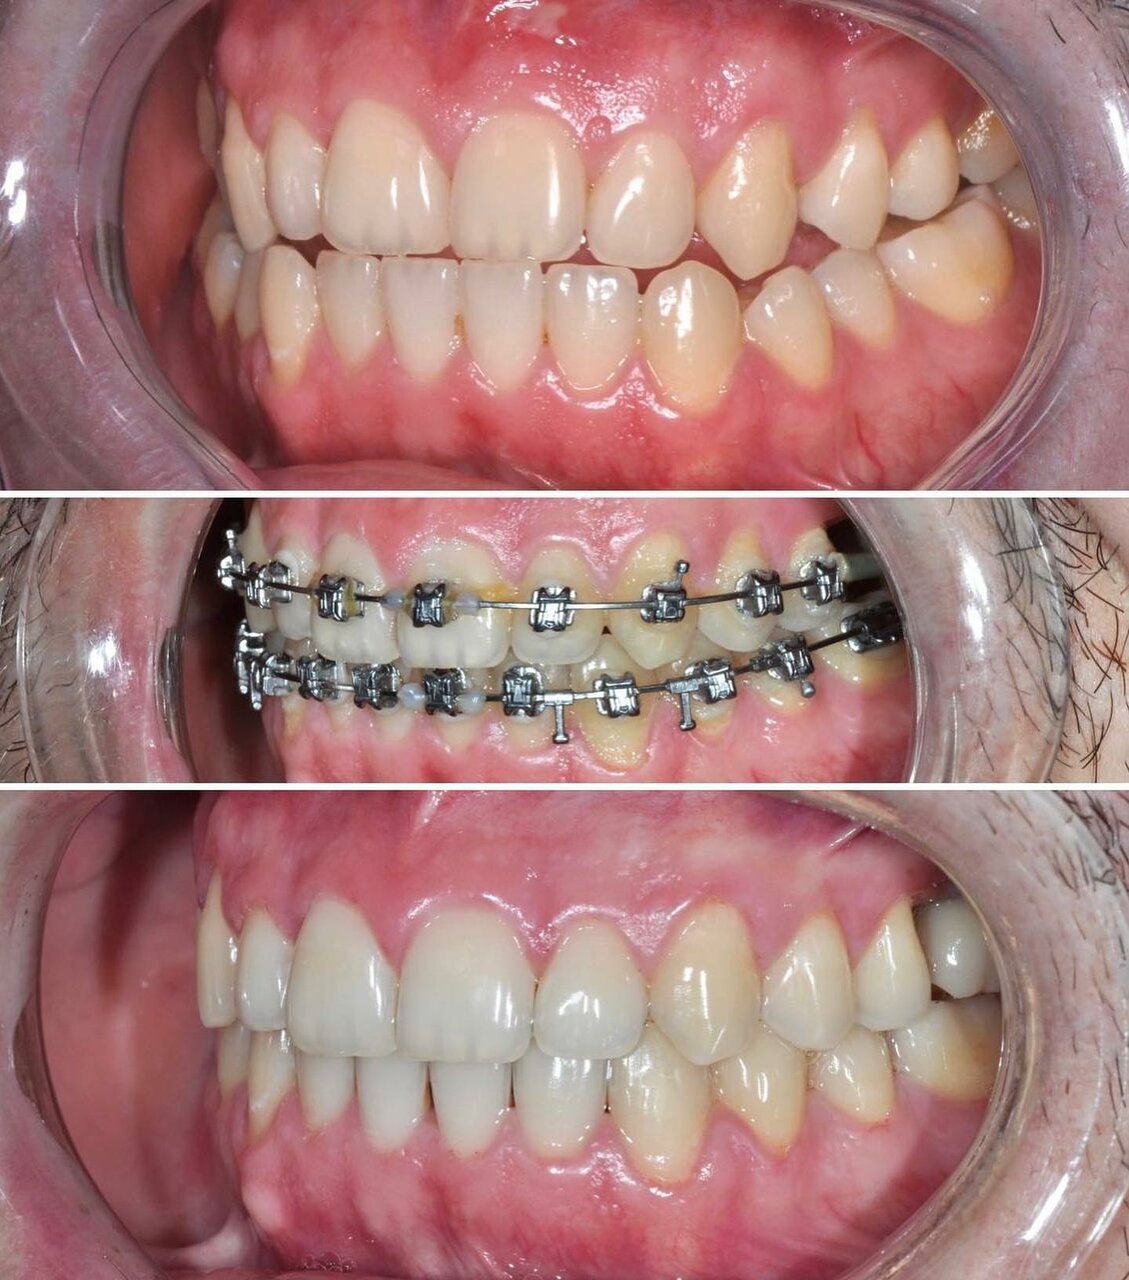

Клиника предоставляет услуги по всем основным направлениям стоматологии, включая общую стоматологию, ортодонтию, хирургическую и эстетическую стоматологию, а также детскую стоматологию. Среди дополнительных услуг: лечение кариеса, пломбирование, удаление зубов, имплантация, протезирование, отбеливание, установка виниров и брекетов, лечение десен и каналов, рентгенография, челюстно-лицевая хирургия и френулопластика.

- ортодонтия

- брекеты

- Положительные впечатления от консультации и установки брекетов.

- Отрицательные последствия лечения (выпадение зубов, испорченный прикус).

- Халатность ортодонта (непунктуальность, некачественное лечение).

- Недовольство качеством ортодонтического лечения (потраченные время и деньги без результата)

Записывался на консультацию и дальнейшую установку брекетов для исправления прикуса. Впечатления на данный момент только положительные. Работа аккуратная, отношение вежливое, дополнительных услуг не навязывали.